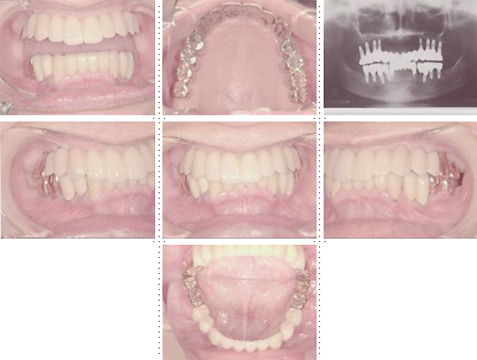

症例2

62才 女性

上顎は総義歯、下顎はブリッジと局部床義歯が装着。義歯は違和感があり、食事も不便を感じ、審美的にも人前にでるのが苦痛に感じていました。この状態を打破するためにも、「インプラント治療に自分の人生を賭けてみたい」という覚悟で来院されました。インプラント手術に対する恐怖心も強くお持ちでした。このような骨幅が狭いケースでは、X線撮影と共にCT撮影による画像診断とインプラント埋入シミュレーションが重要です。

下顎は両側犬歯を残し、他は抜歯。インプラント7本埋入。 上顎はインプラント8本埋入。 インプラント手術を受けられる患者さんは、前の晩眠れない程の不安感、恐怖心を持って来院されます。実際には麻酔注射は痛みを感じず、インプラント手術も痛みも無く、短時間(1本平均3分)で終わるという、当院独自のテクニックにより、2回目からのインプラント手術は気楽になるようです。 前歯は仮歯の段階で患者さん、歯科医、技工士の三者で、審美性・機能性の面から10回以上形態修正を繰り返し検討した後、上・下顎共に前歯・小臼歯はセラミック(MB)クラウン、大臼歯はゴールドクラウンを装着。ご本人とご家族の方にも、「アンチエイジングには、審美インプラント治療が一番効果あり」と大変喜んで頂きました。